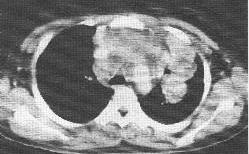

何杰金氏淋巴瘤(CT增强)

何杰金氏淋巴瘤。CT增强纵隔窗扫描示纵隔内广泛轻度强化软组织密度病变,主要位于前、中纵隔,为融合增大淋巴结,病变并侵犯左肺形成肿块。